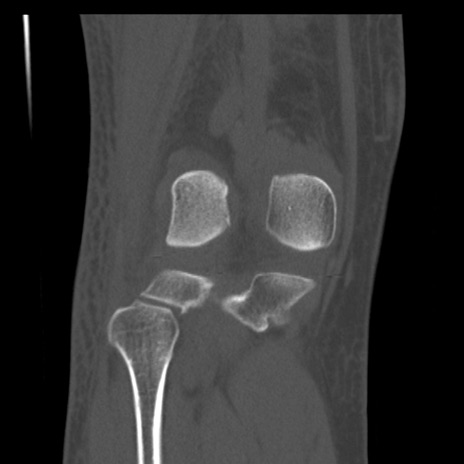

症例28 右膝関節CT(冠状断像)

右膝関節CT